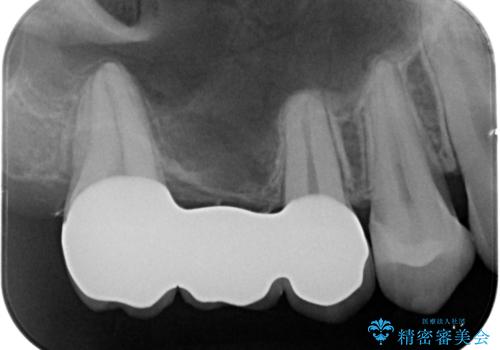

- 銀の詰め物、被せ物を白くしたいとのことで来院。

銀のところはインレーブリッジになっており、外してブリッジを入れたいが奥の歯が前に倒れ込んでおり、

ダミーの歯の部分(ポンティック)のスペースが狭いため無理やり作るとインレーブリッジと同じように小さい歯が出来てきます。

なので親知らずを抜歯して、一番奥の歯を部分矯正(upライト)をして倒れ込んでいる歯を起こしてスペースを作り、ブリッジの治療を行いました。